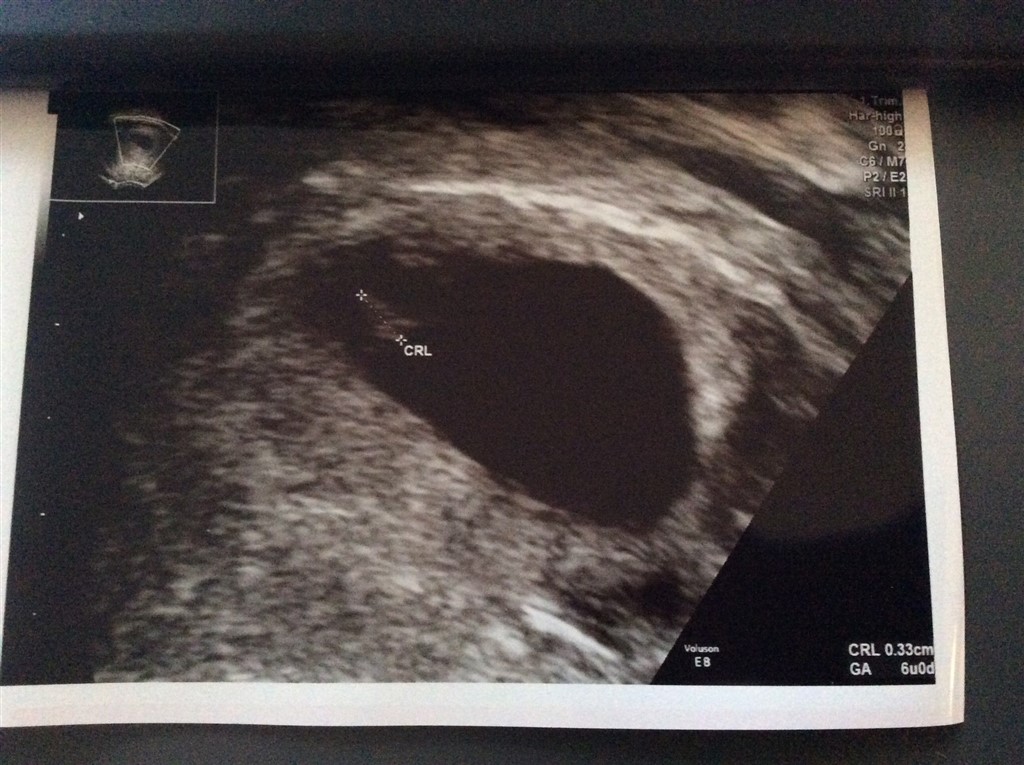

Min første skanning i uge 7+2

Jeg var super glad for at jeg gjorde det. Havde mistet 3 gange før så havde brug for at se liv så hurtigt som muligt.

Vedhæftede fotos (klik for at se i fuld størrelse)